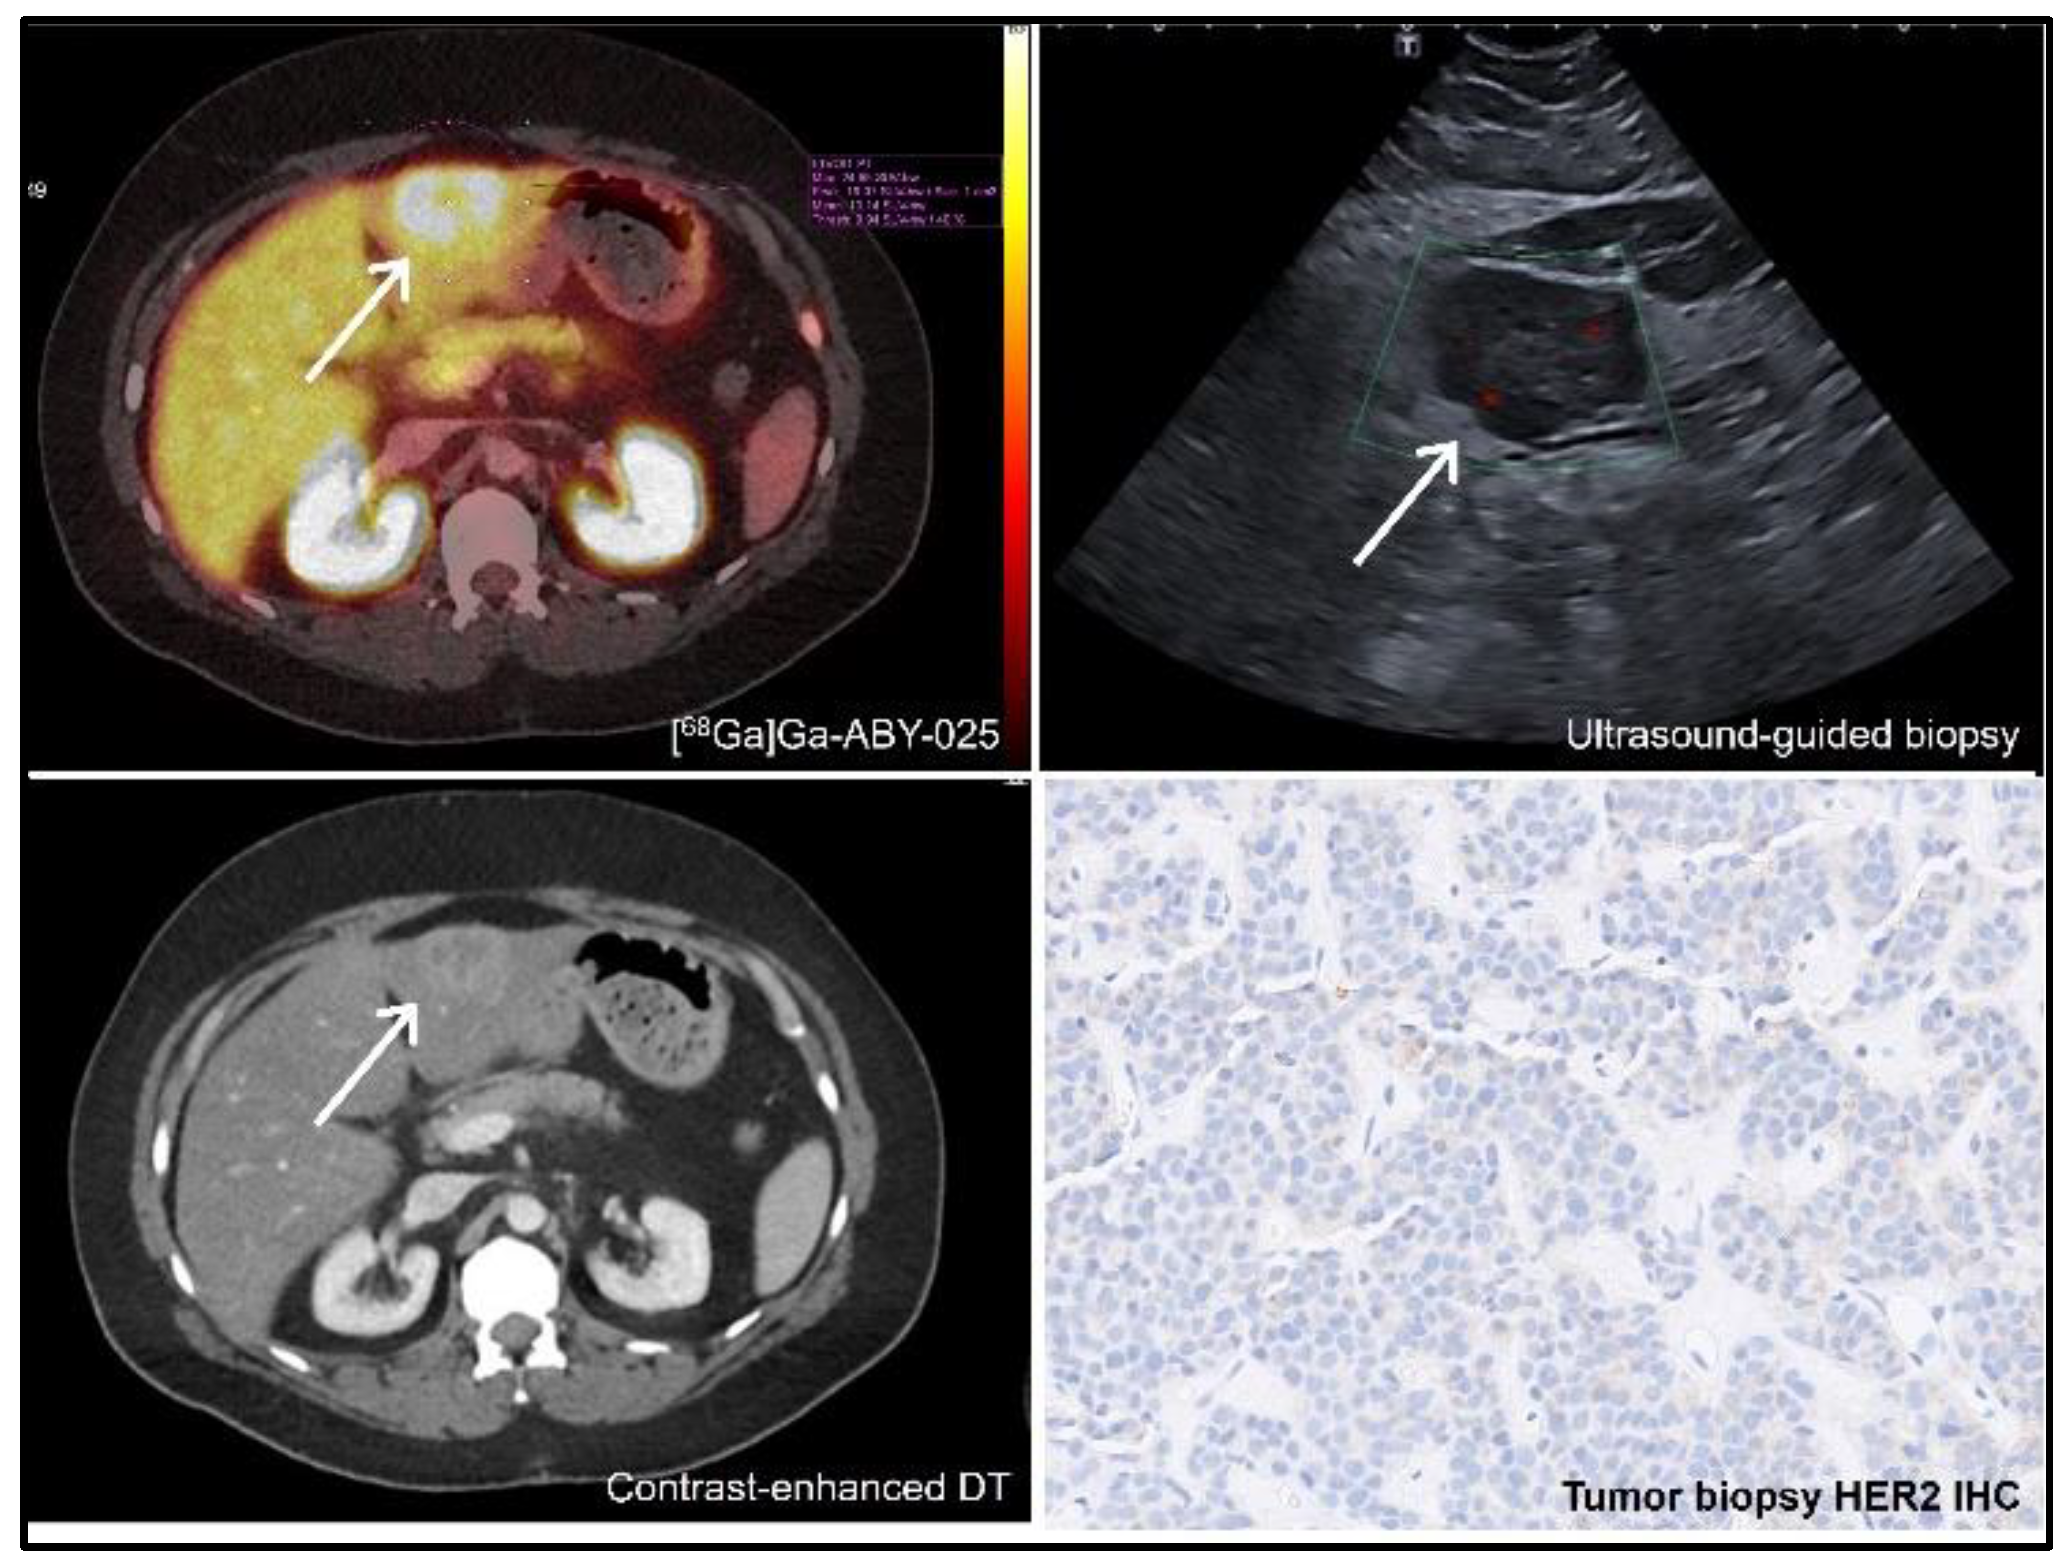

- Sorensen, J.; Velikyan, I.; Sandberg, D.; Wennborg, A.; Feldwisch, J.; Tolmachev, V.; Orlova, A.; Sandstrom, M.; Lubberink, M.; Olofsson, H.; et al. Measuring HER2-Receptor Expression In Metastatic Breast Cancer Using [68Ga]ABY-025 Affibody PET/CT. Theranostics 2016, 6, 262–271. [Google Scholar] [CrossRef] [PubMed]

- Alhuseinalkhudhur, A.; Lindman, H.; Liss, P.; Sundin, T.; Frejd, F.Y.; Hartman, J.; Iyer, V.; Feldwisch, J.; Lubberink, M.; Ronnlund, C.; et al. Human Epidermal Growth Factor Receptor 2-Targeting [(68)Ga]Ga-ABY-025 PET/CT Predicts Early Metabolic Response in Metastatic Breast Cancer. J Nucl Med 2023, 64, 1364–1370. [Google Scholar] [CrossRef] [PubMed]

- Sandberg, D.; Tolmachev, V.; Velikyan, I.; Olofsson, H.; Wennborg, A.; Feldwisch, J.; Carlsson, J.; Lindman, H.; Sorensen, J. Intra-image referencing for simplified assessment of HER2-expression in breast cancer metastases using the Affibody molecule ABY-025 with PET and SPECT. Eur J Nucl Med Mol Imaging 2017, 44, 1337–1346. [Google Scholar] [CrossRef] [PubMed]

- Altena, R.; Buren, S.A.; Blomgren, A.; Karlsson, E.; Tzortzakakis, A.; Brun, N.; Moein, M.M.; Jussing, E.; Frejd, F.Y.; Bergh, J.; et al. Human Epidermal Growth Factor Receptor 2 (HER2) PET Imaging of HER2-Low Breast Cancer with [(68)Ga]Ga-ABY-025: Results from a Pilot Study. J Nucl Med 2024. [Google Scholar] [CrossRef] [PubMed]